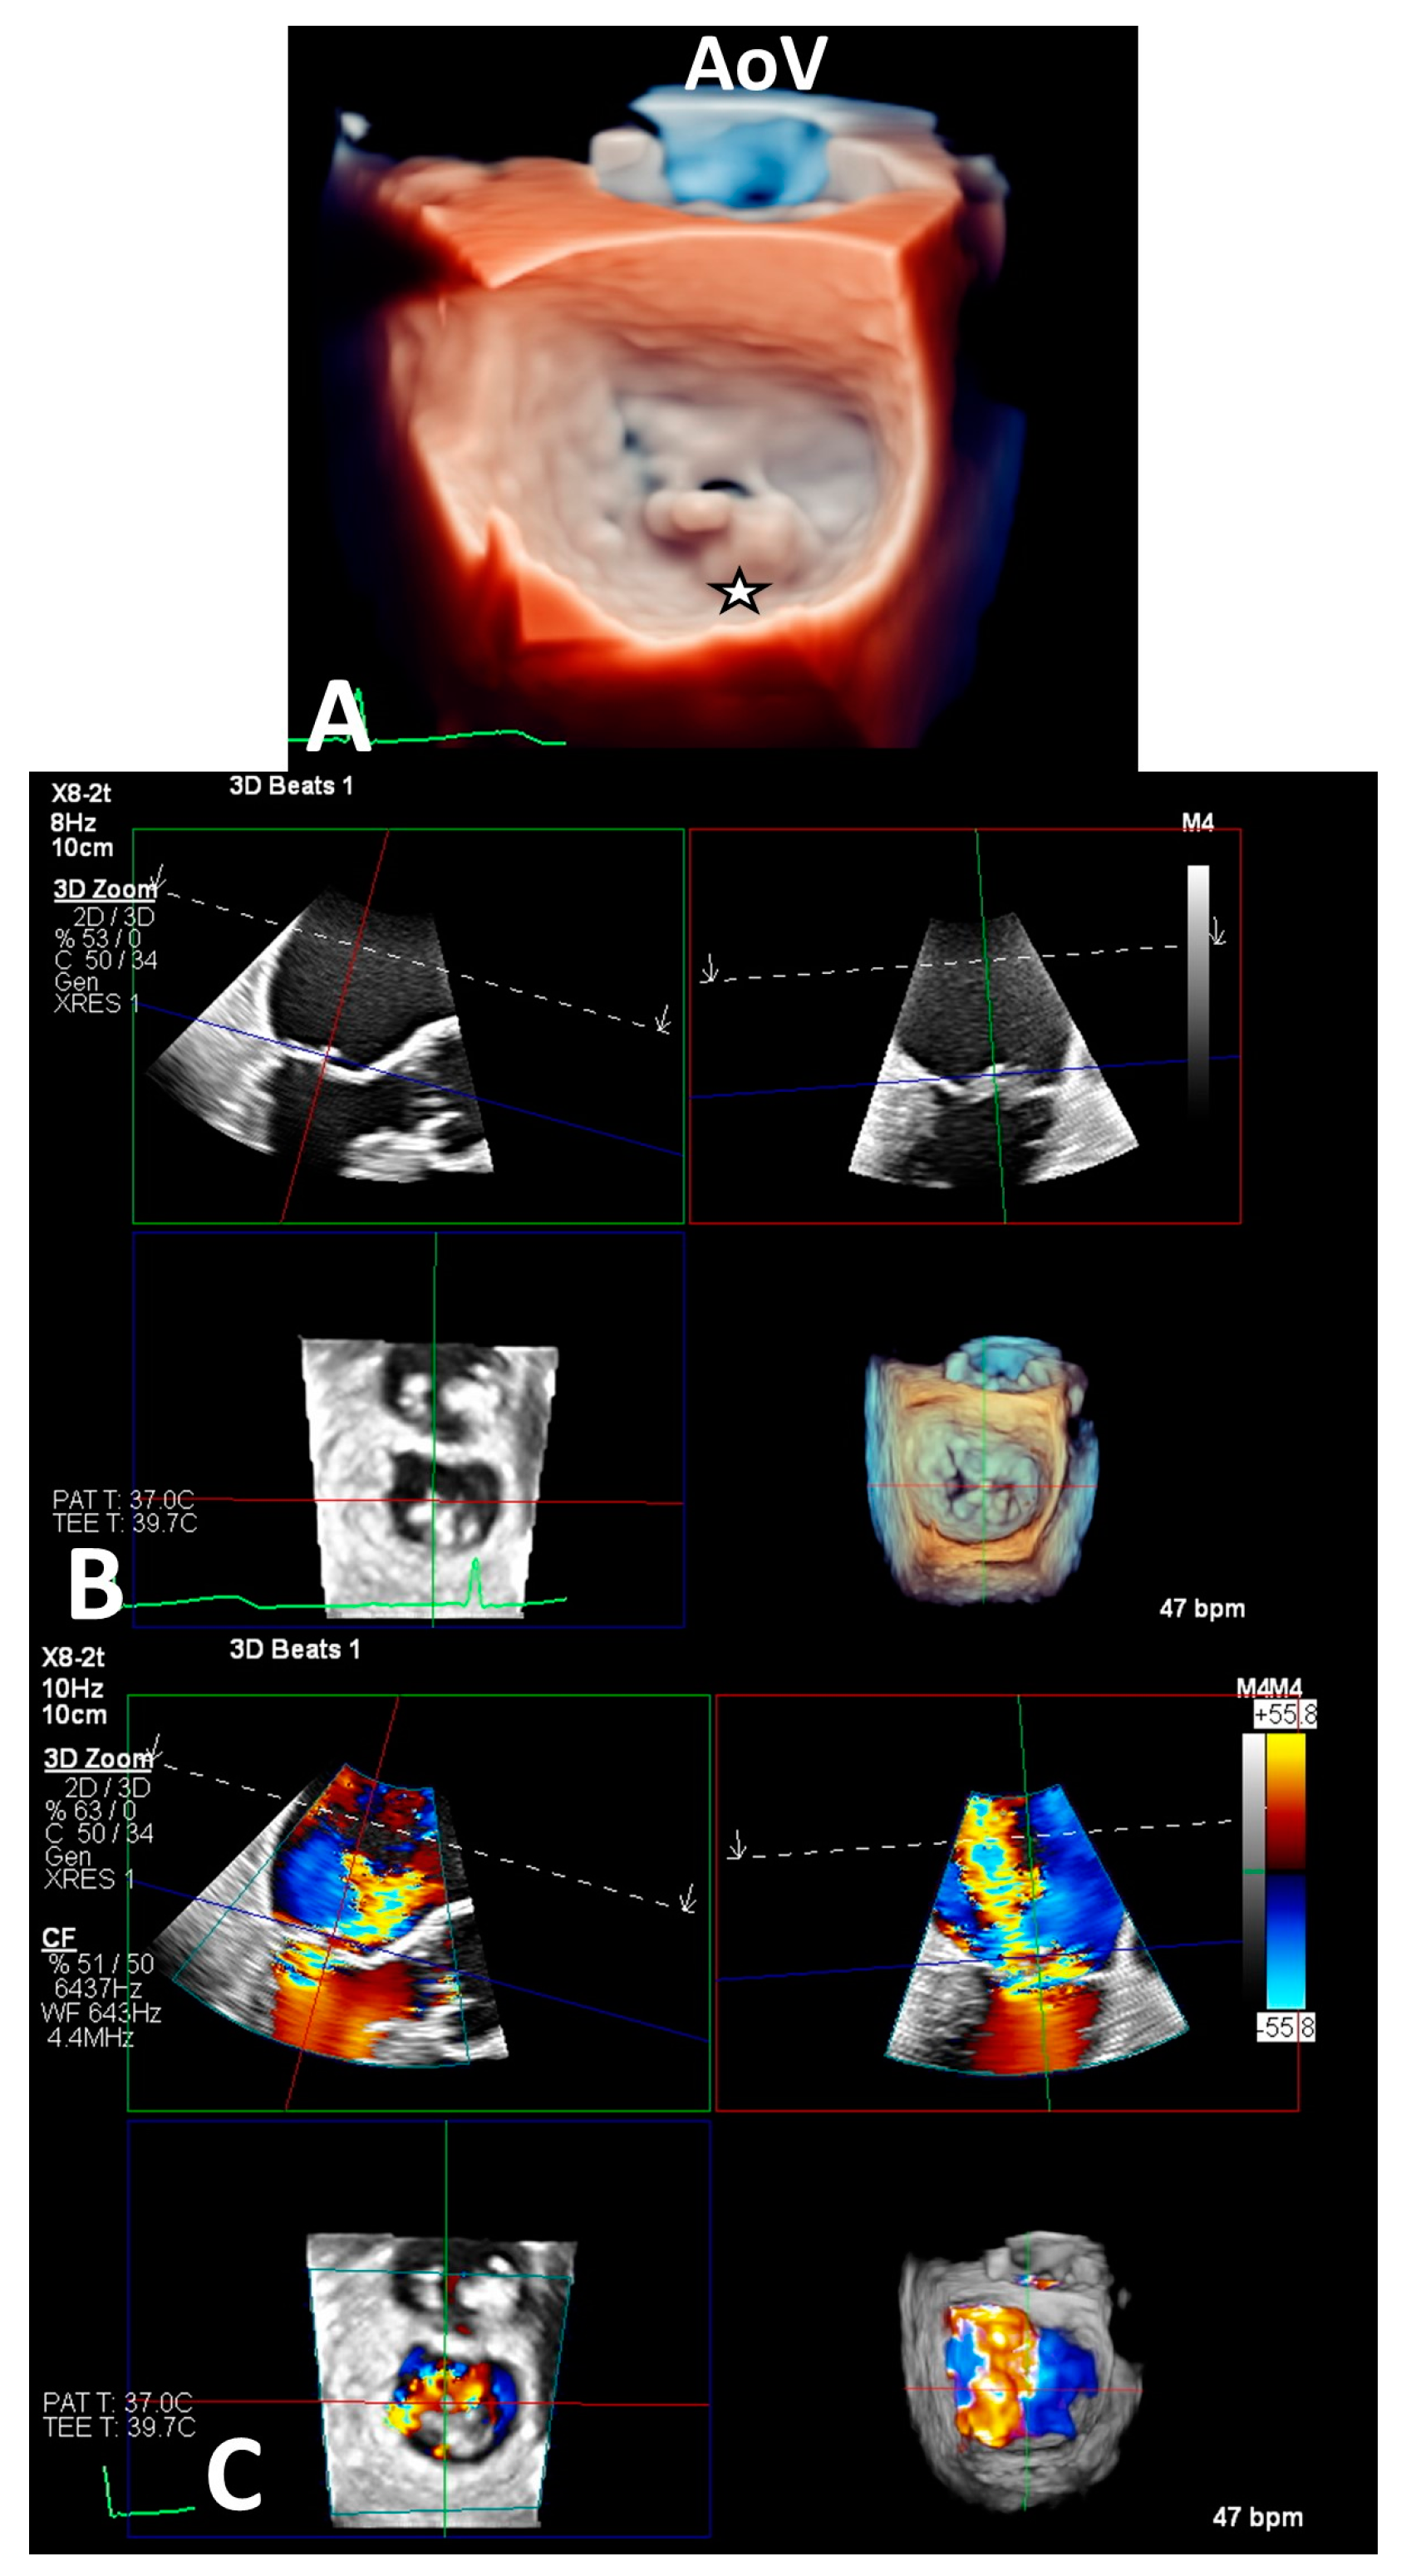

2.5. Imaging Evaluation

2.6. Procedure